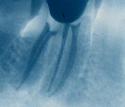

Una vez se ha realizado la limpieza y conformación, se procede al secado mediante puntas de papel y al cierre hermético y tridimensional de cada conducto. Esto se realiza mediante un material llamado "gutapercha",en forma de conos, usado universalmente en endodoncia. Previamente se debe comprobar radiográficamente la longitud y el ajuste del cono principal.

La técnica más extendida consiste en ir sellando el conducto mediante puntas de este material que ajustan a la longitud exacta del conducto (aproximadamente a medio milímetro del final), de esta manera se van aplicando una tras otra y presionando lateralmente hasta que el conducto se ha obturado completamente. Como agente de unión se emplea un cemento específico para endodoncia. Existen también otras técnicas donde la gutapercha se calienta y se compacta verticalmente.

Es muy importante que el conducto quede totalmente obturado a la longitud correcta (de 1 mm a 0,5 mm del final). El material no debe quedar a menos distancia ni pasarse de esta longitud para obtener las mayores posibilidades de éxito.